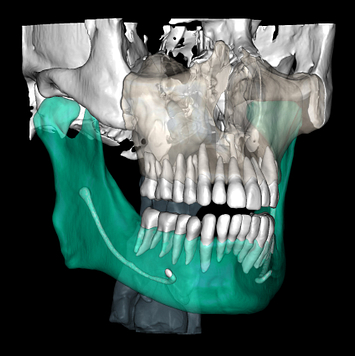

So what is Segmentation? It basically means taking the CBCT and delineating all the different 3D structures, bones, individual teeth, etc.

These can then be individually exported via the software by generating STL files from CBCT dicom data. This can be used in other dental software. Jaw STLs can be used in Modjaw (jaw motion capture) for TMJ analysis, for example. As well as in exocad to help visualize the jaws for surgical planning or guide creation.

- CBCT segmentation

STLs of upper and lower jaws imported into Modjaw for TMJ analysis in jaw motion. this is made possible by CBCT segmentation using Diagnocat.

The surgical crown lengthening guide was made with the aid of maxilla STL to visualize crestal bone level. Again thanks to CBCT segmentation by Diagnocat.

CBCT Segmentation into STL

Generate STL files from CBCT DICOM data.

Generate maxilla and mandible in one STL file or face, teeth, maxilla, mandible, airway, cranial base, canals as separate STL files.